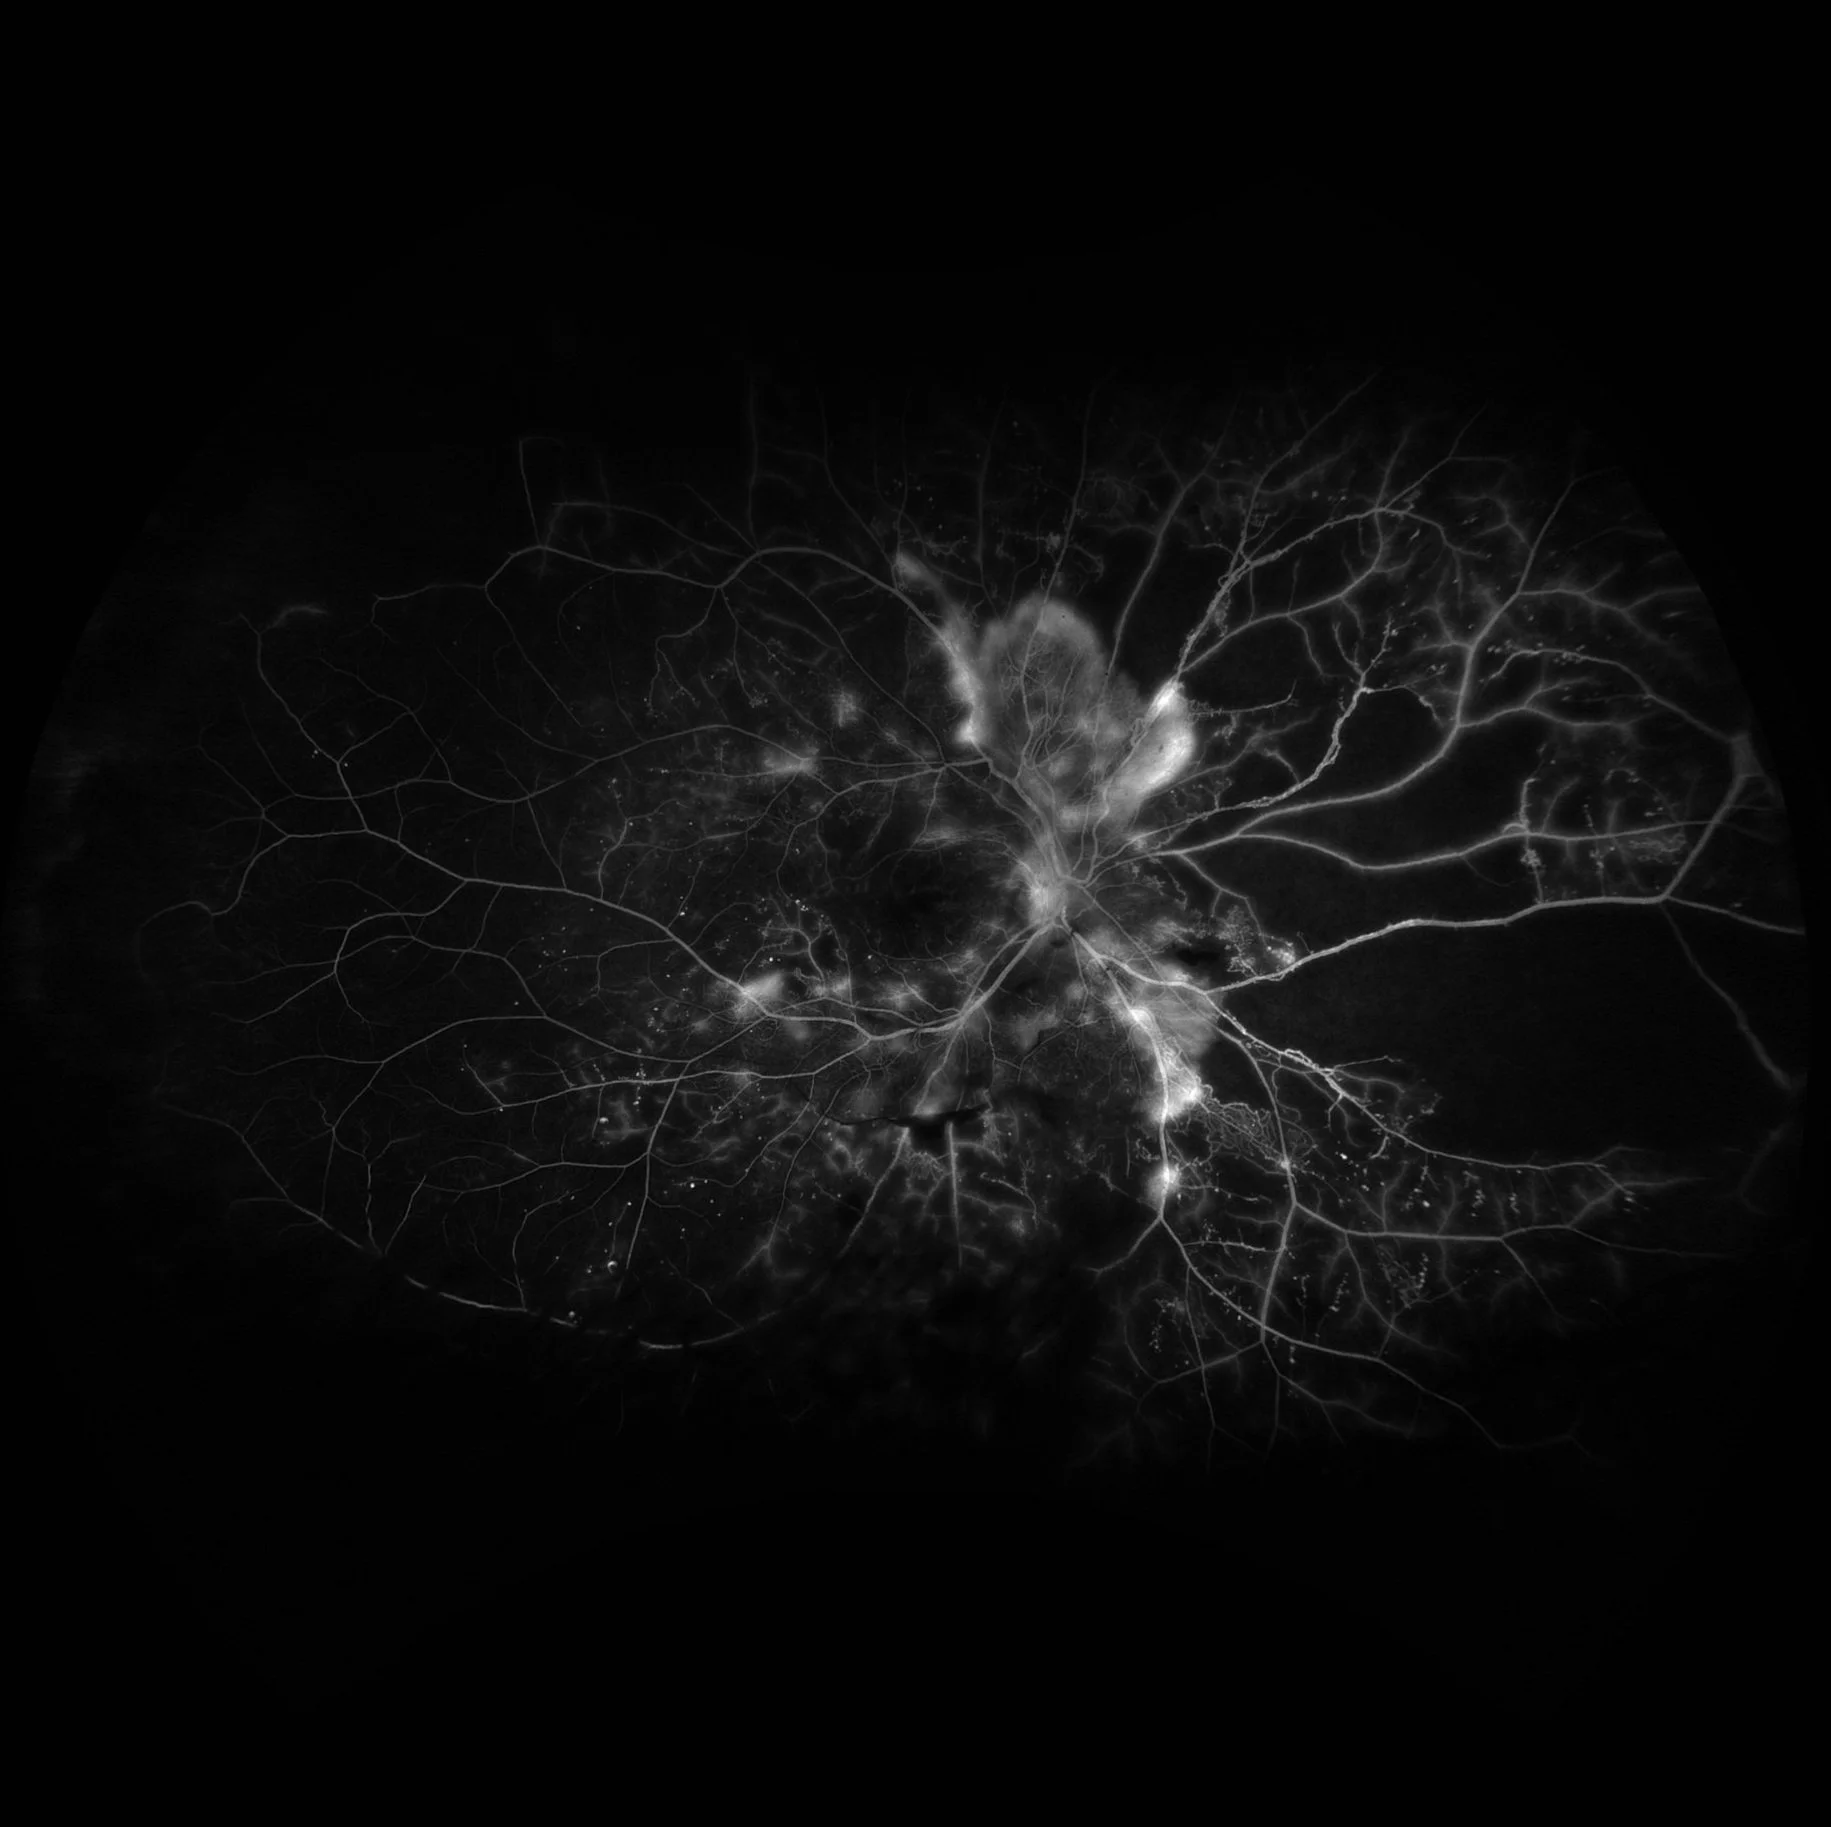

Proliferative Diabetic Retinopathy

This is a severe case of proliferative diabetic retinopathy, with neovascularization at the disc and peri-papillary areas. Abnormal vessel formation, that are friable and leaky, lead to hyperfluorescence with indistinct borders that widens and intensifies as the angiogram progresses.

Notice the extensive occlusive disease and non-perfusion due to capillary drop out in the periphery.